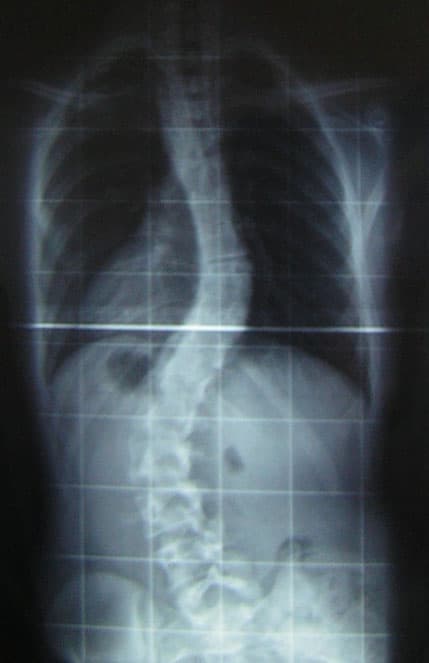

La scoliose est une déviation sinueuse de la colonne vertébrale dans les trois plans de l'espace : inclinaison dans le plan frontal, rotation des vertèbres dans le plan horizontal et inversion des courbures dans le plan sagittal. Il ne faut pas confondre la scoliose avec l'attitude scoliotique qui est une déviation dans un seul plan de l'espace, réductible et temporaire. La scoliose est une déformation permanente et irréductible. Une déviation du rachis est considérée comme une scoliose quand l'angulation est égale ou supérieure à 10 degrés. Environ 4 % des enfants ont un certain degré de rotation de la colonne vertébrale, la plupart ne nécessitant aucune prise en charge. 4 % de la population présente une scoliose d'angulation supérieure à 10°. 0,4 % de la population présente une scoliose supérieure à 20° et peut justifier d'un traitement orthopédique conservateur. 0,2 % de la population présente une scoliose supérieure à 30°. 70 % des scolioses de plus de 20° concerne les filles. La fréquence de la scoliose est multipliée par 10 lorsque l'un des parents au premier degré présente une scoliose. Chez l'adulte, la fréquence de la scoliose est plus importante que chez l'enfant et l'adolescent. Elle concerne 6 % de la population à 40 ans, 10 % à 65 ans et 50% à 90 ans. Les scolioses de l'adulte sont dans la majorité des cas des scolioses de l'enfance ou de l'adolescence qui vieillissent (scolioses vieillissantes). Dans 10% des cas, ce sont des scolioses apparues à l'âge adulte (scolioses de novo), généralement chez la femme post-ménopausée. Ces scolioses sont provoquées par la dégénérescence du rachis liée à l'âge. Il est intéressant de noter que l'ensemble de la population présente une vraie scoliose (avec gibbosité). Cependant, cette déformation reste dans la majorité des cas à l'état endémique et discret, c'est-à-dire inférieure à 10 degrés d'angulation. En effet, durant la poussée de croissance pubertaire, le rachis se déforme souvent de façon naturelle sous l'excès de tonus des chaines musculaires.